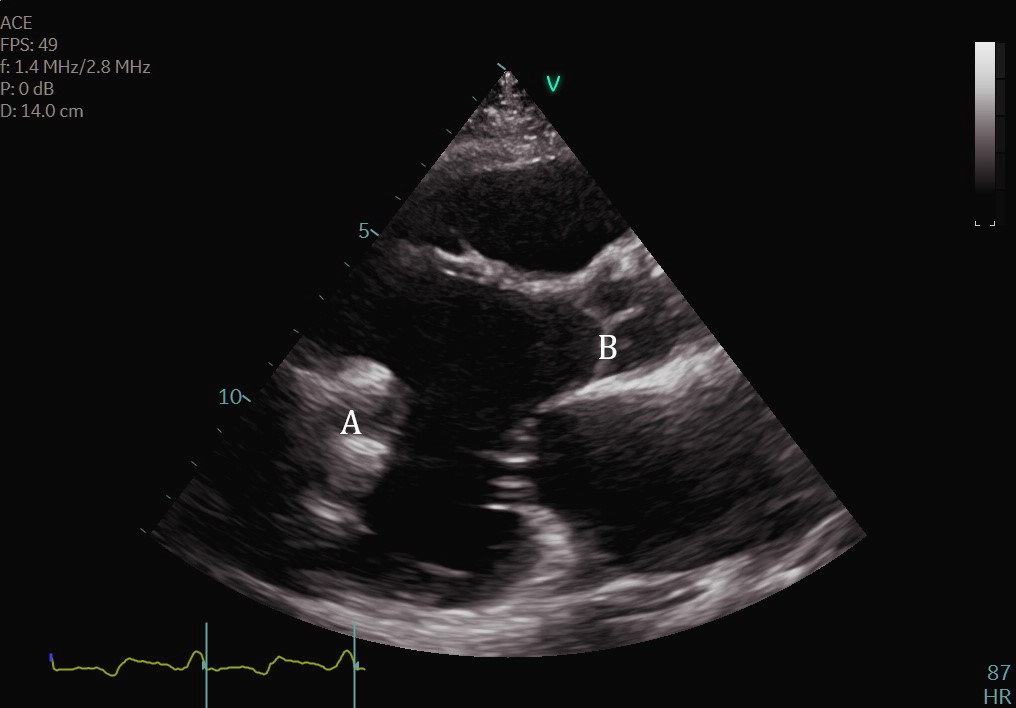

The intra-aortic balloon pump is a percutaneously placed counter pulsation device which helps in decreasing afterload as well as augmenting coronary perfusion. Initially developed in the 1960s it is the oldest MCS device and given its simplicity, cost effectiveness, and ease to implant and explant, it is the most commonly used temporary support device [6]. Although it is typically placed in the cardiac catheterization lab under fluoroscopic guidance, TEE can be utilized to help in its placement in the intubated patient in the intra-operative setting. The femoral artery is the most common site of placement however they can on occasion be placed in alternative sites such as the axillary artery or directly into the aorta [7, 8]. When placed via the femoral artery, it is threaded over a guidewire. TEE can be used to visualize both the guidewire as well as the tip of the IABP catheter during placement (Fig. 1) [9]. Ideal positioning of the balloon tip is 1–2 cm distal to the left subclavian artery to derive maximal hemodynamic benefit [10]. Positioning can be confirmed by visualizing the descending aorta and then withdrawing the TEE probe until the left subclavian artery and aortic arch are visualized. Upon activation of the balloon pump the gas filled balloon will cause shadowing and reverberation artifacts (Fig. 2). Its presence can be used as confirmation of proper function of the device. If these artifacts are not seen or bubbles are visualized in the aorta, rupture of the IABP should be suspected [9]. In addition to hemodynamic monitoring with a Swan-Ganz catheter, TTE can be used to monitor LV function after IABP placement and can help guide weaning of IABP support. It can also visualize any new or worsening aortic regurgitation. Given that IABPs work by reducing afterload, on rare occasions they can precipitate dynamic outflow tract obstruction and paradoxically worsen cardiogenic shock. Examples include patients with a relatively preserved basal or septal myocardial function in scenarios such as takotsubo cardiomyopathy or acute myocardial infarctions. Doppler imaging and color flow doppler can be used to identify such scenarios [11].

Fig. 1.TEE demonstrating IABP in descending aorta (A).

TEE demonstrating IABP in descending aorta (A) with reverberation artifact seen behind it upon activation (B).